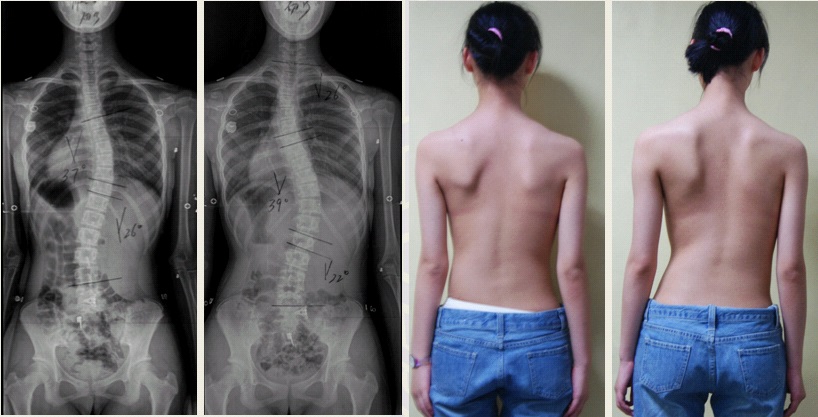

青少年特发性脊柱侧凸(adolescent idiopathic scoliosis, AIS)是一种病因至今未明的三维畸形,发病率约为2%-4%,目前全世界有逾千万AIS患者。作为全球最大的脊柱侧凸矫形中心,鼓楼医院脊柱外科已成功为数千位AIS患者进行手术矫形。为进一步探索AIS病因学基础,邱勇教授带领的研究团队收集了中国长江流域及香港地区总计4317例AIS患者以及6016例正常对照者DNA(为目前全球已知最大的AIS组织样本库),首次利用全基因组芯片技术定位了4个与汉族AIS发病相关的易感基因,包括1p36.32 AJAP1,2q36.1 PAX3,18q21.33 BCL-2和10q24.32 LBX1AS1。上述基因分别与肌肉、软骨发育及细胞凋亡等通路相关,从而为AIS病因学提供了新的线索,并为未来AIS个体化诊疗提供理论基础。